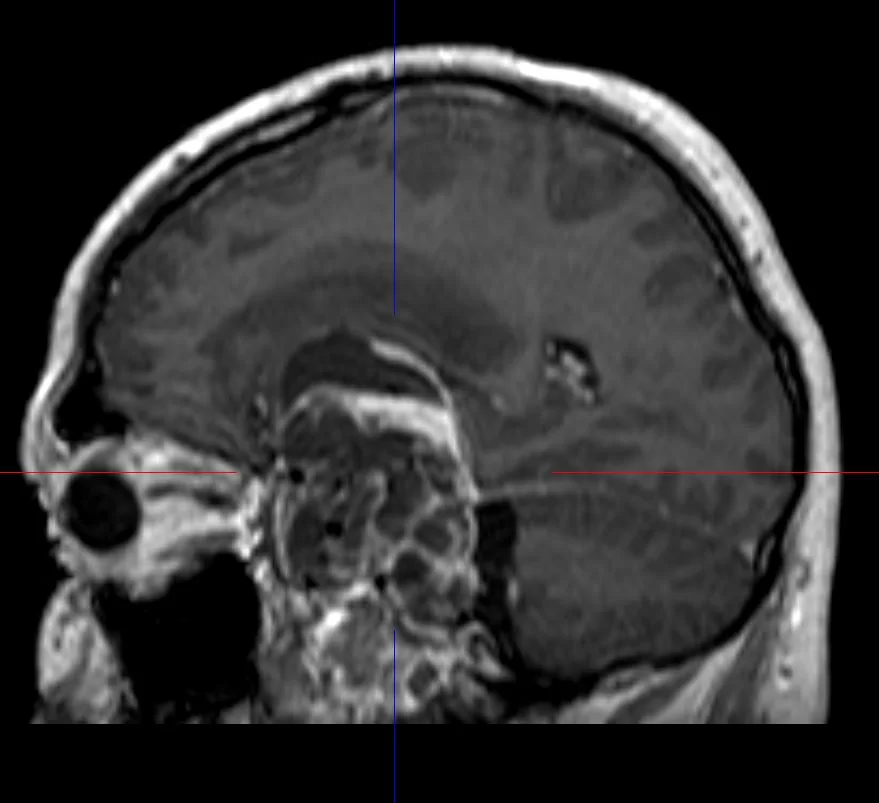

Η μαγνητική τομογραφία εγκεφάλου ανέδειξε εκτεταμένη χωροκατακτητική εξεργασία του μέσου κρανιακού βόθρου, πιθανότατα υποτροπή του δερμοειδούς όγκου για τον οποίο είχε χειρουργηθεί ο ασθενής το 1991.